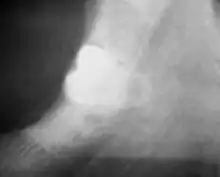

Coronectomy

Coronectomy is a procedure where the crown of the impacted wisdom tooth is removed, but the roots are intentionally left in place. It is indicated when there is no disease of the dental pulp or infection around the crown of the tooth, and there is a high risk of inferior alveolar nerve injury.[31]

Coronectomy, while lessening the immediate risk to the inferior alveolar nerve function has its own complication rates and can result in repeated surgeries. Between 2.3% and 38.3% of roots loosen during the procedure and need to be removed and up to 4.9% of cases require reoperation due to persistent pain, root exposure or persistent infection. The roots have also been reported to migrate in 13.2% to 85.9% of cases.[31]